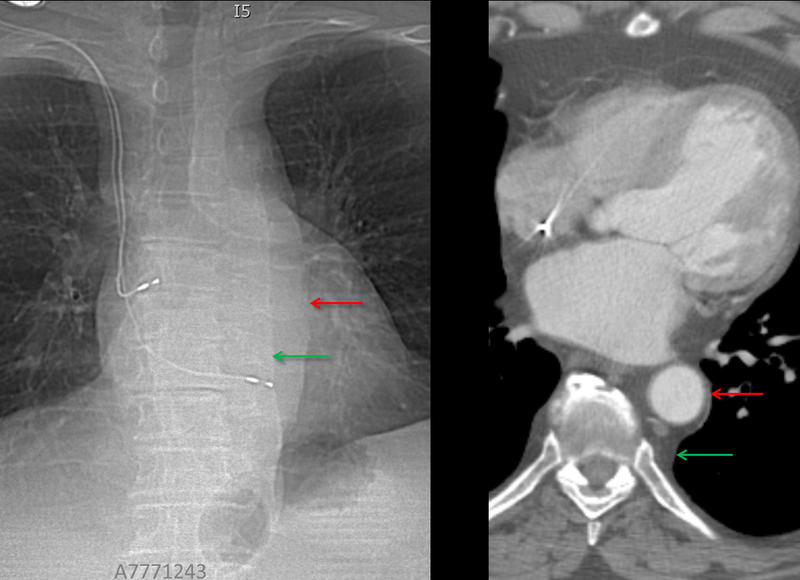

paraspinal "lines"